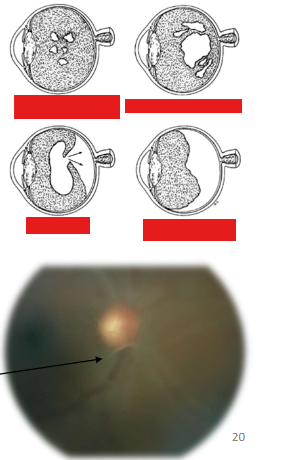

What is this condition

All RD

2nd pic=Tractional

3rd pic=Exudative-pockets where the retina has come off, fluid under retina in the subretinal space

What are the types and causes of retinal detachment?

Rhegmatogenous Retinal Detachment (RRD)

Cause: retinal break

Tractional (TRD, retina pulled away by contracting vitreoretinal membranes eg ERM)

Causes: proliferative DR, retinopathy of prematurity, toxocariasis, trauma, previous giant retinal tear

Exudative (fluid derived from the choriocapillaries gains access to subretinal space)

Causes: neoplastic choroidal lesions, inflammatory disease, optic pit, choroidal coloboma, vascular disorders, nanophthalmos